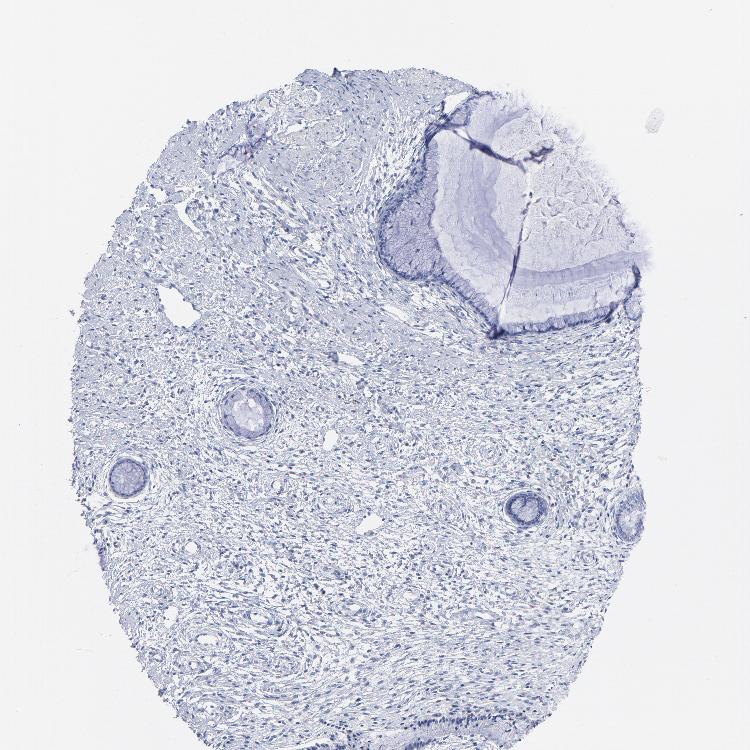

TISSUE PRIMARY DATA CERVIX Show tissue menu

CERVIX - Antibody stainingi

Antibody staining in the annotated cell types in the current human tissue is reported as not detected, low, medium, or high, based on conventional immunohistochemistry profiling in selected tissues. This score is based on the combination of the staining intensity and fraction of stained cells.

Each image is clickable and will lead to virtual microscopy that enables deeper exploration of all samples and also displays staining intensity scores, fraction scores and subcellular localization as well as patient and tissue information for each sample.

Antibody HPA036174Antibody HPA036175Antibody CAB003695

Glandular cells Not detectedLowNot detected

Squamous epithelial cells Not detectedNot detectedNot detected

Information about each individual sample is listed below, including gender, age, a tissue section image and estimated fractions of cell types. nTPM (normalized transcripts per million) values give a quantification of the gene abundance which is comparable between different genes and samples.

Female, age 44

Cervix sample 374

nTPM: 15.4

Cell types%

Glandular cells:

10

Squamous epithelial cells:

5

Smooth muscle cells:

65

Other cell types:

20